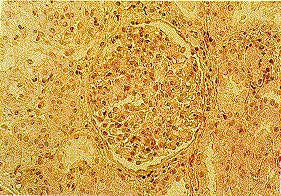

Kidney biopsy (with light, immunofluorescence, and electron microscopy) remains the most sensitive and specific test for definitive diagnosis of GN for patients with nephrotic and nephritic syndromes and rapidly progressive GN.[Figure caption and citation for the preceding image starts]: Minimal change nephropathy: the glomerulus has a normal appearanceFrom: Mason PD, Musey CD. BMJ. 1994 Dec 10;309(6968):1557-63 [Citation ends].

[Figure caption and citation for the preceding image starts]: Diffuse proliferative glomerulonephritis as seen in poststreptococcal glomerulonephritisFrom: Mason PD, Musey CD. BMJ. 1994 Dec 10;309(6968):1557-63 [Citation ends].